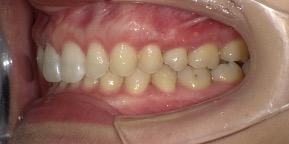

33歳男性のビフォーアフター

| 診断 | 叢生(デコボコがある状態)、上顎前突、オーバージェット |

| 治療方針 | インビザラインシステムにて主にIPR(歯と歯の間をわずかに削合してスペースを獲得する方法)を組み込んだ動的矯正治療を行い、叢生を改善後、保定を行う。臼歯部の咬合関係はプランの関係上ある程度の所までとし、叢生と前歯部の咬合改善を目指した。 |

| 治療費 ※ | 68万8千円(診断、型取り、PMTC、保定装置を含む料金) |

| 治療期間 | 3年 |

| リスク | 1日20時間以上マウスピースを使用できない場合、歯が動かない可能性がある。装着時や食事時に痛みを伴う。歯肉退縮や虫歯になるおそれがある。また、指導通りに装着できていない場合や適切なブラッシングが出来ていないとそのリスクが高くなる。歯根が短くなることがある。ごくまれに歯の神経が損傷してしまうことがある。過去にぶつけたり深い虫歯治療をしたことがあるとそのリスクはやや高くなる。矯正後には保定装置が必要。適切な使用ができない場合、後戻りの原因となる。将来的に歯並びが動いて再矯正が必要な場合がある。親知らずが正常に生えていない場合、その可能性がやや高くなる。 |